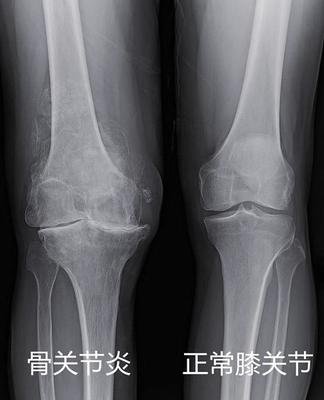

一张膝关节X光片,是膝关节炎的标准检查,也是最简单,最便宜,最有价值的。

关节间隙很狭窄了 这种一般需要换关节了

如果x光片报告上告诉你,“退行性改变”、“骨赘形成”、“间隙变窄”、“髁间嵴变尖”、“软骨下骨硬化/囊变”,这些都是关节炎患者,常常出现的。